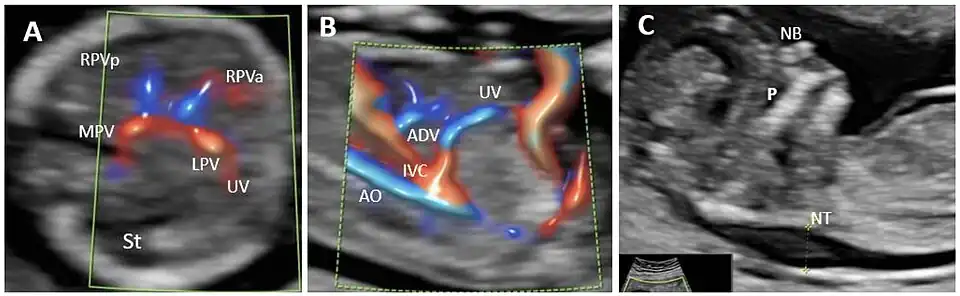

Agenese van ductus venosus (ADV) in een geval van het eerste trimester met drainage van de navelstrengader in de onderste vena cava (IVC) en verhoogde nekplooi. (A): Dwarsvlak van de FT-foetale buik, met high-definition directionele power Doppler toegepast. Er is een “H”-vormige variant van de intrahepatische poortaderverbinding geïdentificeerd; (B): high-definition directionele power Doppler in het sagittale vlak van de foetale buik (hetzelfde geval) toont ADV met drainage van de navelstrengader in de onderste vena cava; (C): mid-sagittale weergave van het foetale gezicht met de maat van de verdikte NT. MPV hoofdpoortader, St maag, LPV linker poortader, UV navelstrengader, RPVa anterieure tak van rechter poortader, RPVp posterieure tak van rechter poortader, Ao aorta, IVC inferior vena cava, ADV ductus venosus agenese, P gehemelte, NB neusbeen, NT nekplooi.